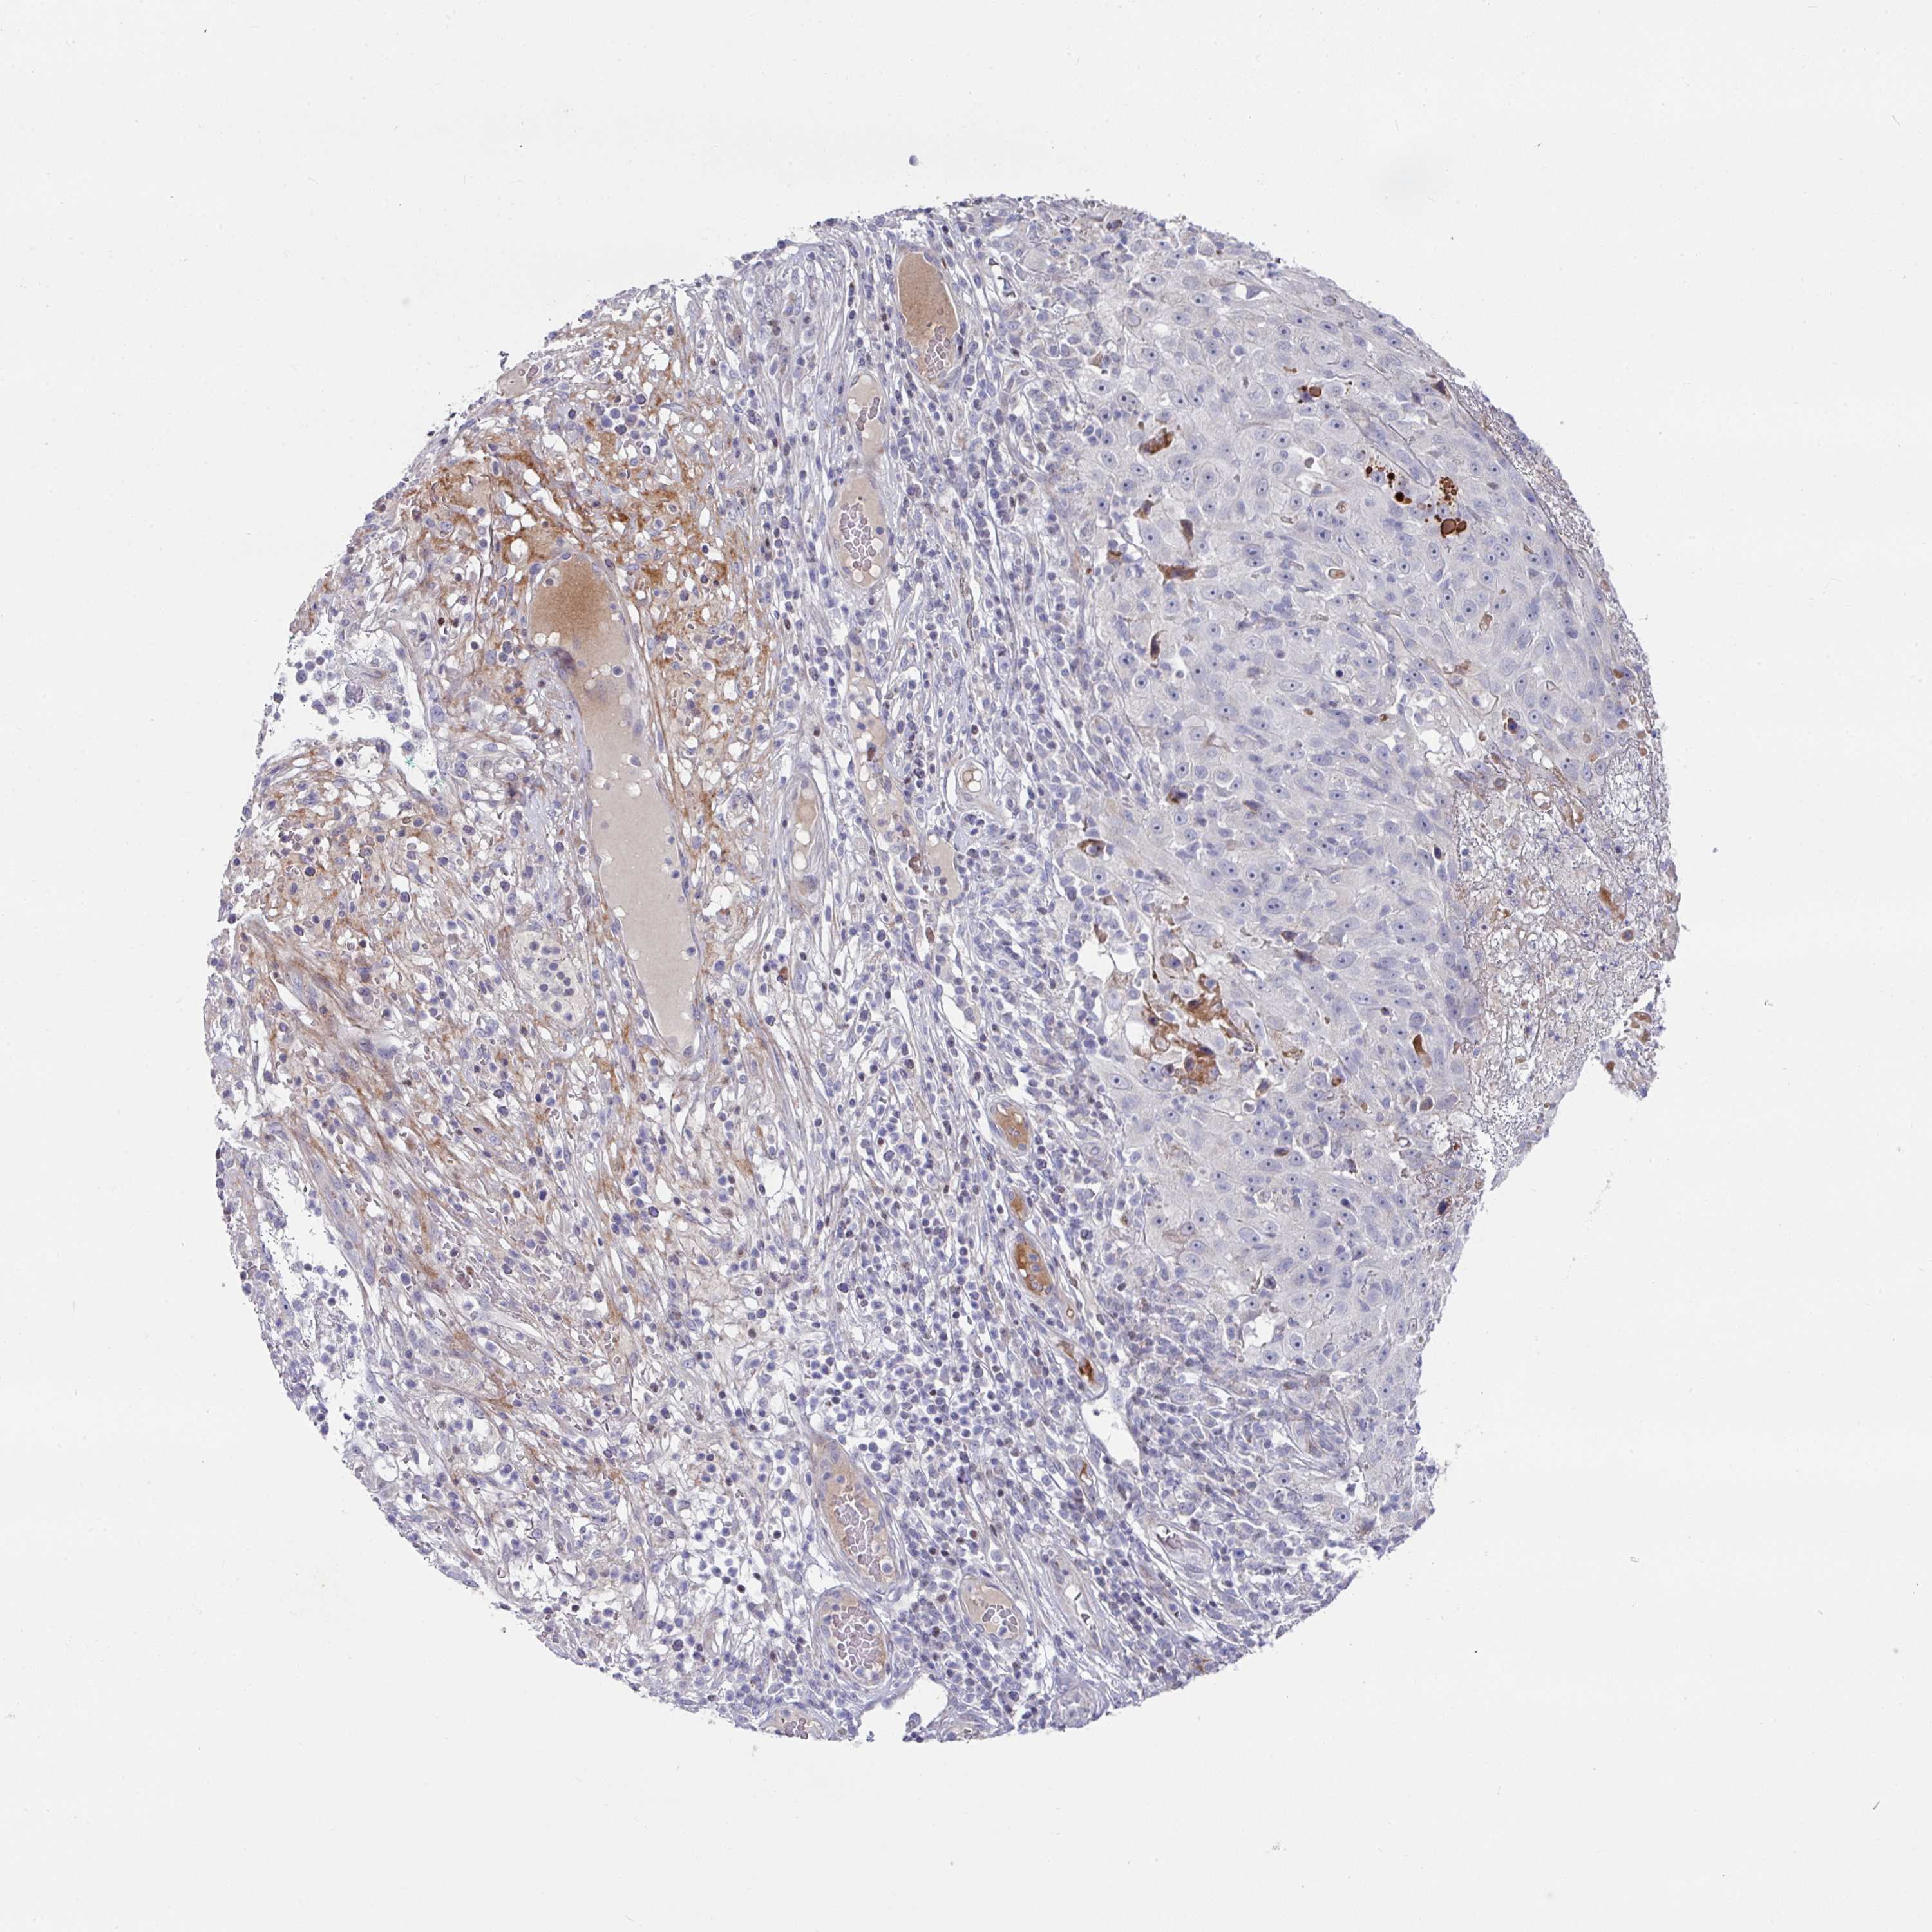

Basal cell and squamous cell cancer

SKIN CANCER - Protein expressioni

A mouse-over function shows sample information and annotation data. Click on an image to view it in a full screen mode. Samples can be filtered based on level of antibody staining by selecting one or several of the following categories: high, medium, low and not detected. The assay and annotation is described here.

Each image is clickable and will lead to virtual microscopy that enables deeper exploration of all samples and also displays staining intensity scores, fraction scores and subcellular localization as well as patient and tissue information for each sample.

Antibody CAB011574

Staining

High

Medium

Low

Not detected

Intensity

Strong

Moderate

Weak

Negative

Quantity

>75%

75%-25%

<25%

None

Location

Nuclear

Cytoplasmic/membranous

Cytoplasmic/membranous,nuclear

Squamous cell carcinoma, metastatic, NOS